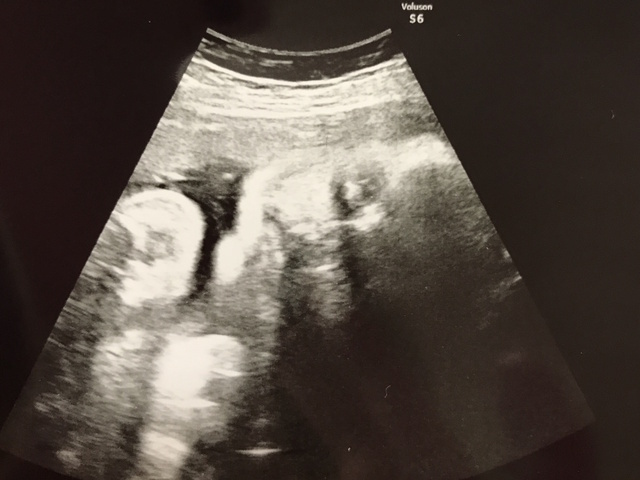

37週0日(37w0d・女の子)|aada1254さん(25歳)

エコー写真撮影時のエピソード:

顔がここまでハッキリと分かるエコー写真は初めてだったので、とても感動的でした。色々な人に見せてあげたい1枚です(^^)

正産期に入り出産も待ち遠しいこの頃なので、実際どんな顔の子が出てくるのか、今から楽しみです!